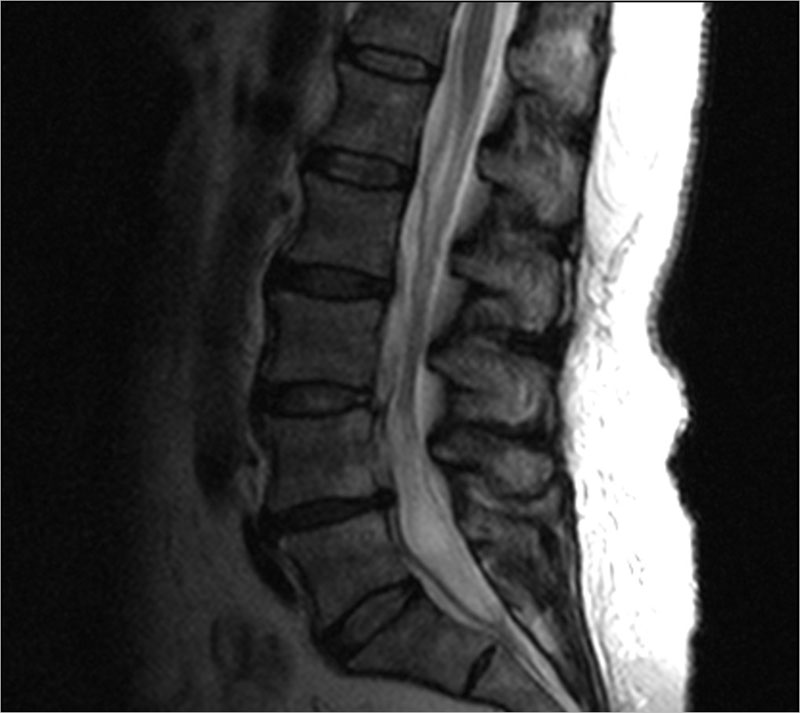

МРТ позвоночника (шейного, грудного и поясничного отделов) позволяет визуализировать структуры позвоночника (кости, нервы, мышцы, связки, диски) и подчас МРТ позволяет обнаружить патологию которую не удается диагностировать с помощью КТ, МСКТ, рентгенографии.

МРТ позвоночника позволяет обнаружить изменения, как в позвоночнике, так и в окружающих тканях (например, инфекции или опухоли).

• Обнаружить изменения в межпозвонковых дисках (протрузия или грыжа диска), наличие компрессии корешков, что является причиной радикулитов

• Выявить участки позвоночника, где есть сужение спинального канала (стеноз) и требуется оперативное лечение

Примеры исследований